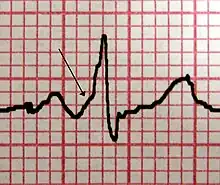

| Conduction through the accessory pathway results in a delta wave. | |

| A characteristic "delta wave" (arrow) seen in a person with Wolff–Parkinson–White syndrome. Note the short PR interval. | |

WPW is commonly diagnosed on the basis of the electrocardiogram in an asymptomatic individual. In this case, it is manifested as a delta wave, which is a slurred upstroke in the QRS complex that is associated with a short PR interval. The short PR interval and slurring of the QRS complex are reflective of the impulse making it to the ventricles early (via the accessory pathway) without the usual delay experienced in the AV node.

When an individual is in normal sinus rhythm, the ECG characteristics of WPW are a short PR interval (less than 120 milliseconds in duration), widened QRS complex (greater than 120 milliseconds in duration) with slurred upstroke of the QRS complex, and secondary repolarization changes (reflected in ST segment-T wave changes).

In individuals with WPW, electrical activity that is initiated in the SA node travels through the accessory pathway, as well as through the AV node to activate the ventricles via both pathways. Since the accessory pathway does not have the impulse slowing properties of the AV node, the electrical impulse first activates the ventricles via the accessory pathway, and immediately afterwards via the AV node. This gives the short PR interval and slurred upstroke of the QRS complex known as the delta wave.